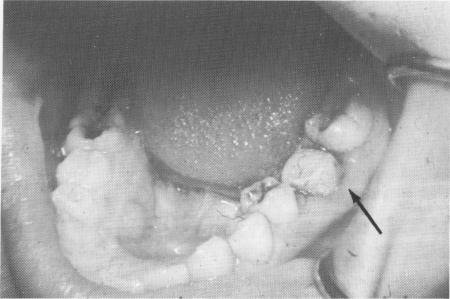

Fig. 8-71. A vent-plant is screwed into the interseptal bone buccal to the remaining lingual half of the tooth.

In this case, an unusual approach was taken to prevent good neighboring teeth from being sacrificed for full crown restorations. A 13-year-old girl had sagittally fractured a 6-year mandibular molar exactly in half vertically downward to the apices of the roots in a mesiodistal direction. The canals were also severed exactly in half, so that root canal therapy was impossible. The buccal half of the tooth was removed (Fig. 8-70), and a vent-plant was screwed through the bone remaining between the mesiobuccal and distobuccal roots (Fig. 8-71). The protruding shaft of the implant and the lingual half of the molar tooth were notched and locked together with acrylic (Fig. 8-72). The acrylic was prepared (Fig. 8-73) and an impression taken for a full crown gold veneer, which was cemented in position with hard cement (Fig. 8-74). A radio-